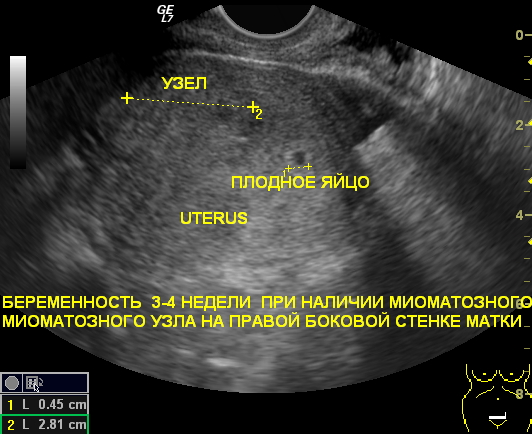

Регулярные ультразвуковые исследования миомы матки во время беременности имеют огромное значение. В период вынашивания малыша уровень эстрогена в организме возрастает, что приводит к активному делению клеток в тканях матки. Это может стать причиной появления миомы. Кроме того, уже существующие миомы могут начать увеличиваться в размерах. Поэтому проведение ультразвуковых исследований во время беременности становится крайне важным.

Миома во время беременности

Крупные опухоли могут существенно усложнить процесс родов. Они могут вызывать кровотечения в процессе родов и затруднять прохождение ребенка через родовые пути. Также возможно физическое сжатие плода. Кроме того, миомы могут нарушать работу плаценты, что приводит к недостаточному поступлению питательных веществ к ребенку. Именно поэтому важно проводить регулярные обследования на наличие опухолей во время беременности.